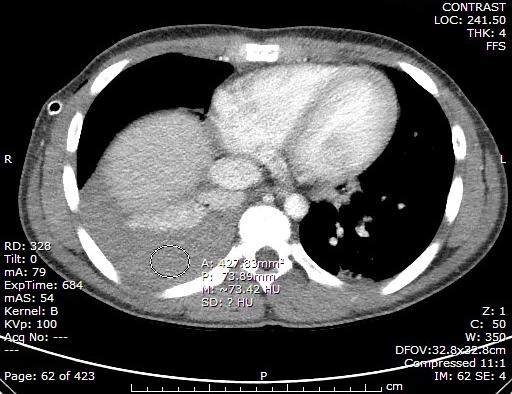

A previously healthy 13 year old male presented to the ER with a 1 day history of cough, right-sided chest pain, and dizziness. There was no recent illness, fever, travel, drug use, or sputum production. Physical examination demonstrated dullness to percussion and right-sided egophony on chest exam with no crackles or wheeze. Extremities were cool, capillary refill 3 seconds. CBC showed WBC 15.2 k/cumm (neutrophils 83%, lymphocytes 10%, monocytes 7%, eosinophils 1%, basophils 0%), hemoglobin 12.2 GM/dL, hematocrit (Hct) 36.8%, platelets 239 k/cumm. CT chest demonstrated the following:

Pleural fluid analysis revealed: grossly bloody, total nucleated cell count 3,850/cumm (54% neutrophils, 20% lymphocytes, 1% eosinophils, 25% monocytes), pleural fluid Hct 35%.